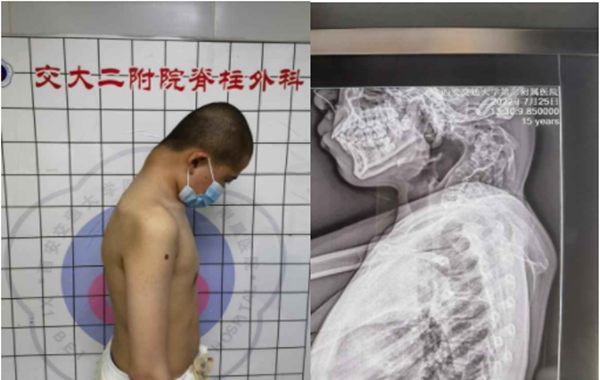

近日,我院骨二科成功为15岁的小患者实施了颈椎后凸截骨矫形术,目前患者恢复良好,术前的双上肢麻木无力等症状明显改善,已下床进行康复锻炼,并已于日前出院。

来自青海的小患者,2年前,家人便发现其颈椎后方鼓起大包,随着年龄增长,包块也日益增大,在当地医院拍片显示为:颈椎后凸畸形,前后在多家医院就诊但均对治疗束手无策。近半年来,患者出现双侧上肢无力,麻木等症状,且越来越严重,家长辗转于多家医院就诊,均因为手术难度太大,风险极高而被婉拒。患者家属打听到李浩鹏教授在脊柱畸形的矫形方面有着丰富的经验,并成功救治大量脊柱畸形方面的患者,最终慕名前来西安交通大学第二附属医院骨二科。

据文献报道,颈椎后凸≥30°即称为重度的颈椎后凸畸形,并且在颈椎过屈过伸时后凸角度改变小于50%称为僵硬性后凸畸形。而该患者,其后凸角度达到110°,且在过屈过伸位置上后凸角度几乎没有变化。对于这种严重且僵硬的颈椎后凸畸形,手术的目的不光是解决畸形的问题,同时还需完成脊髓的减压,给受损的脊髓神经根创造恢复的空间。然而手术的风险和困难也来源于此,在矫正僵硬颈椎畸形时,会在短时间内使颈椎以及脊髓的空间位置发生剧烈的改变,在这一过程中,如何避免原本脆弱的脊髓张力增加而导致四肢瘫痪,是一个严重而极富挑战性的难题。这么严重的畸形,国内外都没有成熟的治疗标准,国内也仅仅几家大医院开展过类似手术,而且只是零星的个案报道。李浩鹏主任医师团队结合这个患者特点,详细评估每张影像学资料,为患者制定了术前牵引,手术先前路松解,再后路截骨固定,再次前路固定的周详的治疗方案。